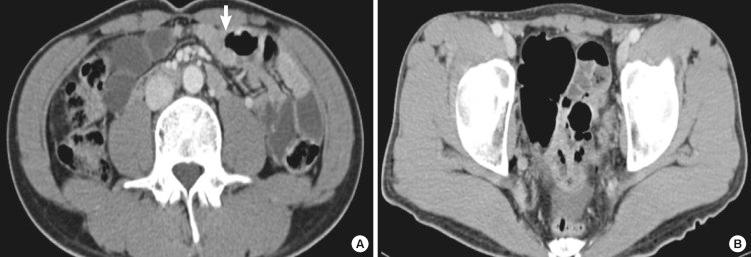

Familial Mediterranean fever (FMF) is known to be a genetic disorder that prevalent among populations surrounding the Mediterranean Sea. Since Mediterranean fever gene (MEFV) was discovered at 1997, some cases have been reported in countries not related or close to this area like Japan. In addition it has been generally accepted that the clinical onset of FMF begins before 20 yr of age in most patients. Onset of the disease at an older age may occur but is rare. Adult-onset FMF may be a form of disease with distinct clinical, demographic and molecular characteristics. We describe a case of adult-onset FMF confirmed by DNA analysis of the MEFV gene in a Korean patient. A 32-yr-old man, who has no family history of FMF, presented with periodic fever, abdominal pain and vomiting. Though several various tests were thoroughly performed to evaluate the cause of his symptoms, there was no evidence of infectious, autoimmune or neoplastic diseases. Several gene analysis of periodic fever syndrome was finally performed and two point mutations (p.Leu110Pro, p.Glu148Gln) were identified. We confirmed the first adult case of FMF through detection of MEFV gene mutations in Korea and describe his clinical characteristics.

家族性地中海热(FMF)是一种已知的遗传性疾病,在地中海周围的人群中较为普遍。自 1997 年发现地中海热基因(MEFV)以来,一些与该地区没有关联或不接近的国家,如日本,也有病例报告。此外,人们普遍认为 FMF 的临床发病通常在大多数患者 20 岁之前。虽然发病年龄较大的情况也可能发生,但较为罕见。成人发病的 FMF 可能是一种具有独特临床、人口统计学和分子特征的疾病形式。我们描述了一例韩国患者通过 MEFV 基因突变 DNA 分析确诊的成人发病 FMF 病例。一名 32 岁的男性,无 FMF 家族史,表现为周期性发热、腹痛和呕吐。尽管为了评估其症状的病因进行了多项详细检查,但没有感染、自身免疫或肿瘤性疾病的证据。最终进行了几项周期性发热综合征的基因分析,发现了两个点突变(p.Leu110Pro,p.Glu148Gln)。我们通过检测 MEFV 基因突变在韩国证实了首例成人 FMF 病例,并描述了他的临床特征。